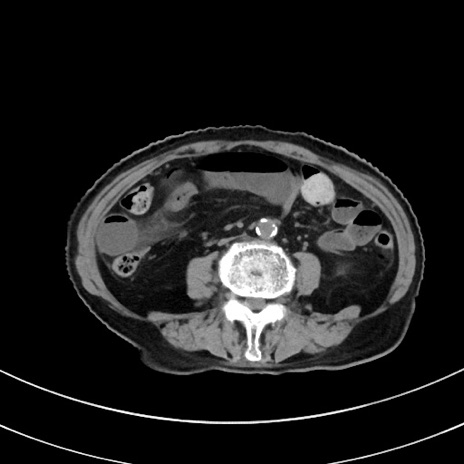

症例33(横断像)

【症例】70歳代 女性

【主訴】心窩部痛

【現病歴】延髄病変の精査・加療にて神経内科入院中。本日より心窩部痛あり。

【既往歴】虫垂炎

【身体所見】右下腹部を中心に圧痛と反跳痛あり。

【データ】WBC 10900、CRP 0.02